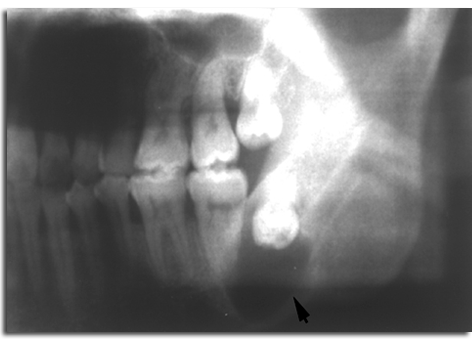

性多见;发病部位以下颌第三磨牙区最常见,其次为上颌单尖牙、上颌第三磨牙和下颌前磨牙区,可能与这些部位的牙齿易于阻生有关;含牙囊肿内所含的牙齿大多数为恒牙,偶见含乳牙或额外牙;囊肿生长缓慢,早期无自觉症状,往往因牙齿未萌、缺失或错位而行X线检查时被发现。囊肿发育较大时可引起颌骨膨隆或面部不对称、牙齿移位及邻近牙的牙根吸收;X线表现为圆形透射区,边界清楚,囊腔内可含一个未萌的牙冠,少数较大的病变也可呈多房性改变。

牙旁囊肿(paradental cyst)是一种特殊类型的炎症性根侧囊肿(inflammatory collateralcyst),发生于阻生下颌第三磨牙的颊侧或远中颊侧,患者常有冠周炎反复发作史,牙齿为活髓;X线显示部分阻生的下颌第三磨牙远中有边界清楚的透射区,有时病变可延伸至根尖部。镜下见囊壁内衬无角化的复层鳞状上皮,厚薄不一,结缔组织囊壁内有大量炎症细胞浸润,部分囊壁可见胆固醇结晶裂隙和异物巨细胞反应。虽然其镜下表现与根尖囊肿相似,但根尖囊肿的患牙为死髓牙,而牙旁囊肿的伴随牙为活髓;在临床上,牙旁囊肿还易与发育性根侧囊肿相混淆,但后者一般不伴有炎症。该囊肿常累及根分叉区,检查见大多数受累牙有所谓釉突(enamel spur)延伸至根分叉处,提示囊肿的发生可能与炎症刺激导致该处的结合上皮增生有关。